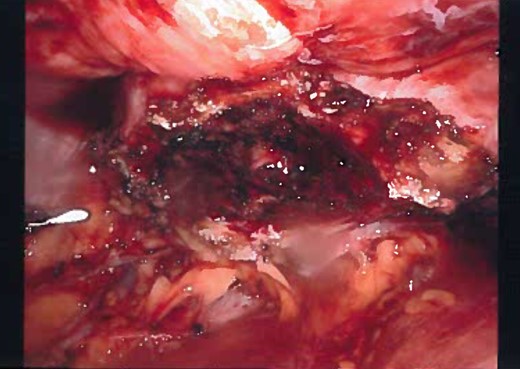

Laparoscopic view of the urachus while dissection, view of the dome of the bladder and dissection of median umbilical ligament.

Laparoscopic view of the dissection, most of the cyst is dissected and over-sewing the dome of the bladder.

Gross appearance of the urachal cyst resembled an inflammatory and necrotic appearance with multiple cystic cavities (Figs 3 and 7). On pathology, tentative diagnosis of the specimen was confirmed as an urachal cyst. The appearance of an ulcerated cyst wall noted with marked fibrosis, acute and chronic inflammation with focal abscess, foreign body giant cells, and fibrous adhesions, consistent with history of infected urachal cyst and no evidence of malignancy. Intra-operative culture of urachal cyst provided contents positive for Escherichia coli, and negative for fungal material. The patient had an uneventful post-operative course. We followed up the patient in 2 weeks and again in 3 months in the outpatient clinic. During the follow-up, patient reported that removal of the cyst helped her abdominal pain, urinary tract symptoms have completely resolved and constipation was improve pertinently.